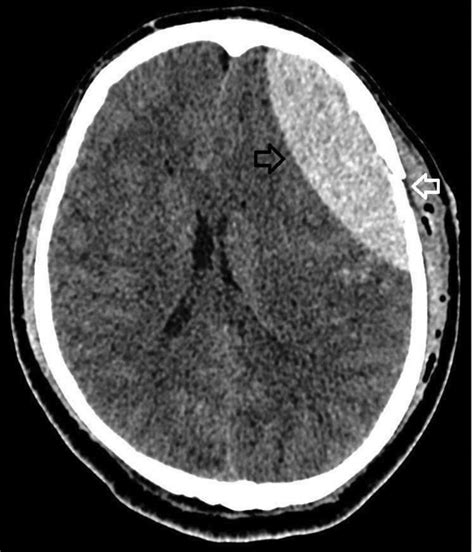

- Vaizdinis tyrimas: Pagrindinis diagnostikos įrankis yra galvos kompiuterinė tomografija (KT), kuri greitai gali atskleisti hematomos buvimą. KT tyrimas parodo kraujo kolekciją, paprastai išgaubtos formos, tarp kaukolės ir kietosios smegenų dangalos.

KT tyrimai atskleidžia subdūrinius ar epidurinius hematomas 20% nesąmoningų žmonių.